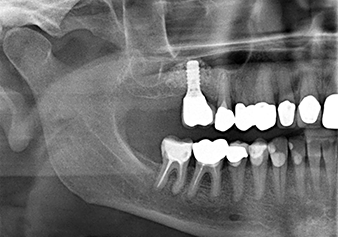

Для перемещения аугментационного материала в направлении верхнечелюстной пазухи атравматично, имплантат вводился очень медленно вручную (рис. 9). При этом мембрана еще раз выталкивалась в краниальном направлении. Через два месяца место операции зажило без раздражения. Через шесть месяцев рентгеновский контроль показал значительное увеличение помутнения, что свидетельствует об оссификации (рис. 10). Протезирование было проведено металлокерамической коронкой.

The x-ray check shows a largely homogeneous peri-implant hard tissue structure

Рис.10: Через шесть месяцев, после установки окончательной керамической коронки, рентгеновский снимок показывает в основном однородную структуру твердых тканей периимплантата.